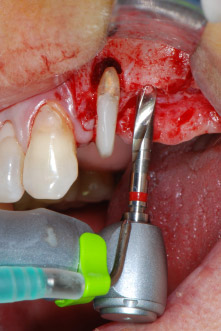

En el siguiente paso, los lechos del implante se prepararon en las posiciones 25 y 26 con instrumentos rotatorios, utilizando un contra-ángulo con un coeficiente de transmisión de 20:1 (WS-75 L, W&H), junto con el nuevo potente motor de implantes Implantmed de W&H (figuras 8 y 19).

El lecho del implante se preparó con el nuevo motor de implantes Implantmed de W&H, en combinación con un contra-ángulo específicamente diseñado para cirugía oral e implantología.

El coeficiente de transmisión de 20:1, junto con el alto torque de hasta 6,2 Ncm del motor de implantes, permite una preparación a baja velocidad, así como la inserción del implante y el corte de roscas. La preparación final hasta la membrana del seno se realizó de nuevo con la unidad piezoeléctrica y un inserto de diamante redondo (Piezomed S2 de W&H).